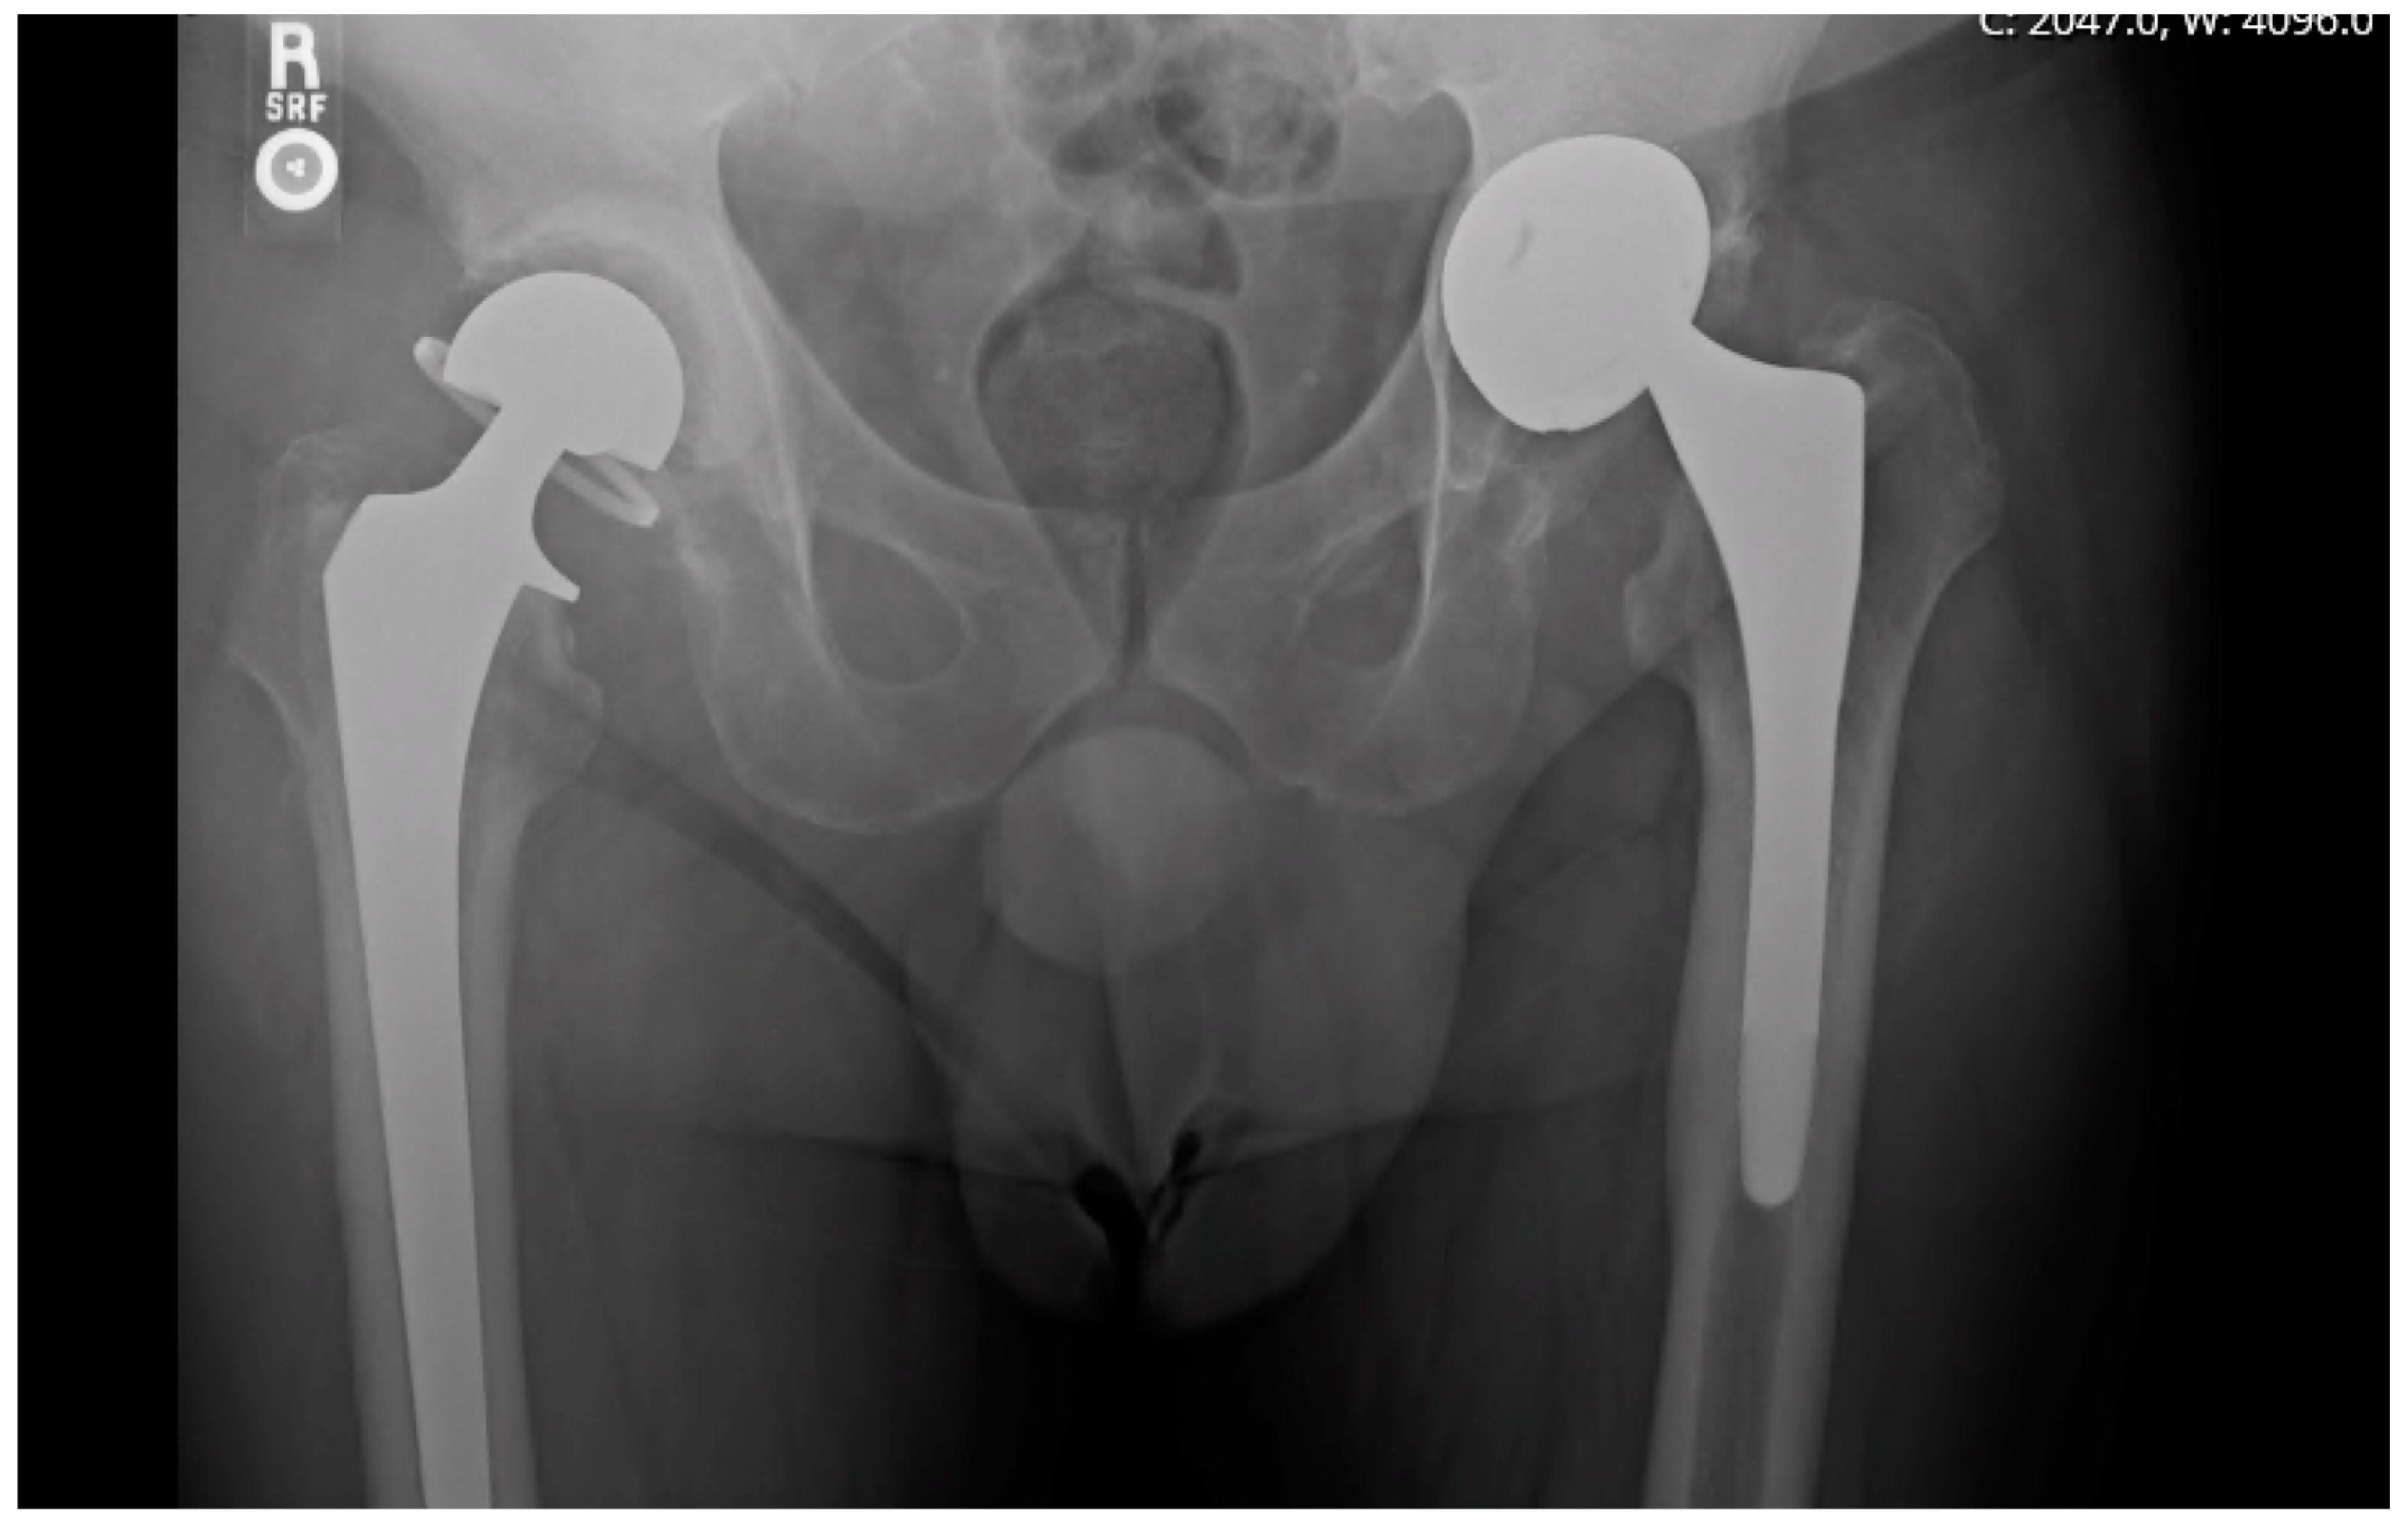

Revision Total Hip Replacement OrthoInfo AAOS Can An Artificial Hip Pop Out  It usually occurs from a significant. The risk is greatest in the first months after surgery. Hip dislocation is a painful event in which the ball joint of your hip comes out of its socket. The problem usually starts with a popping or slipping sensation. Dislocation of an artificial hip is uncommon but may occur within the first three months. Can An Artificial Hip Pop Out.